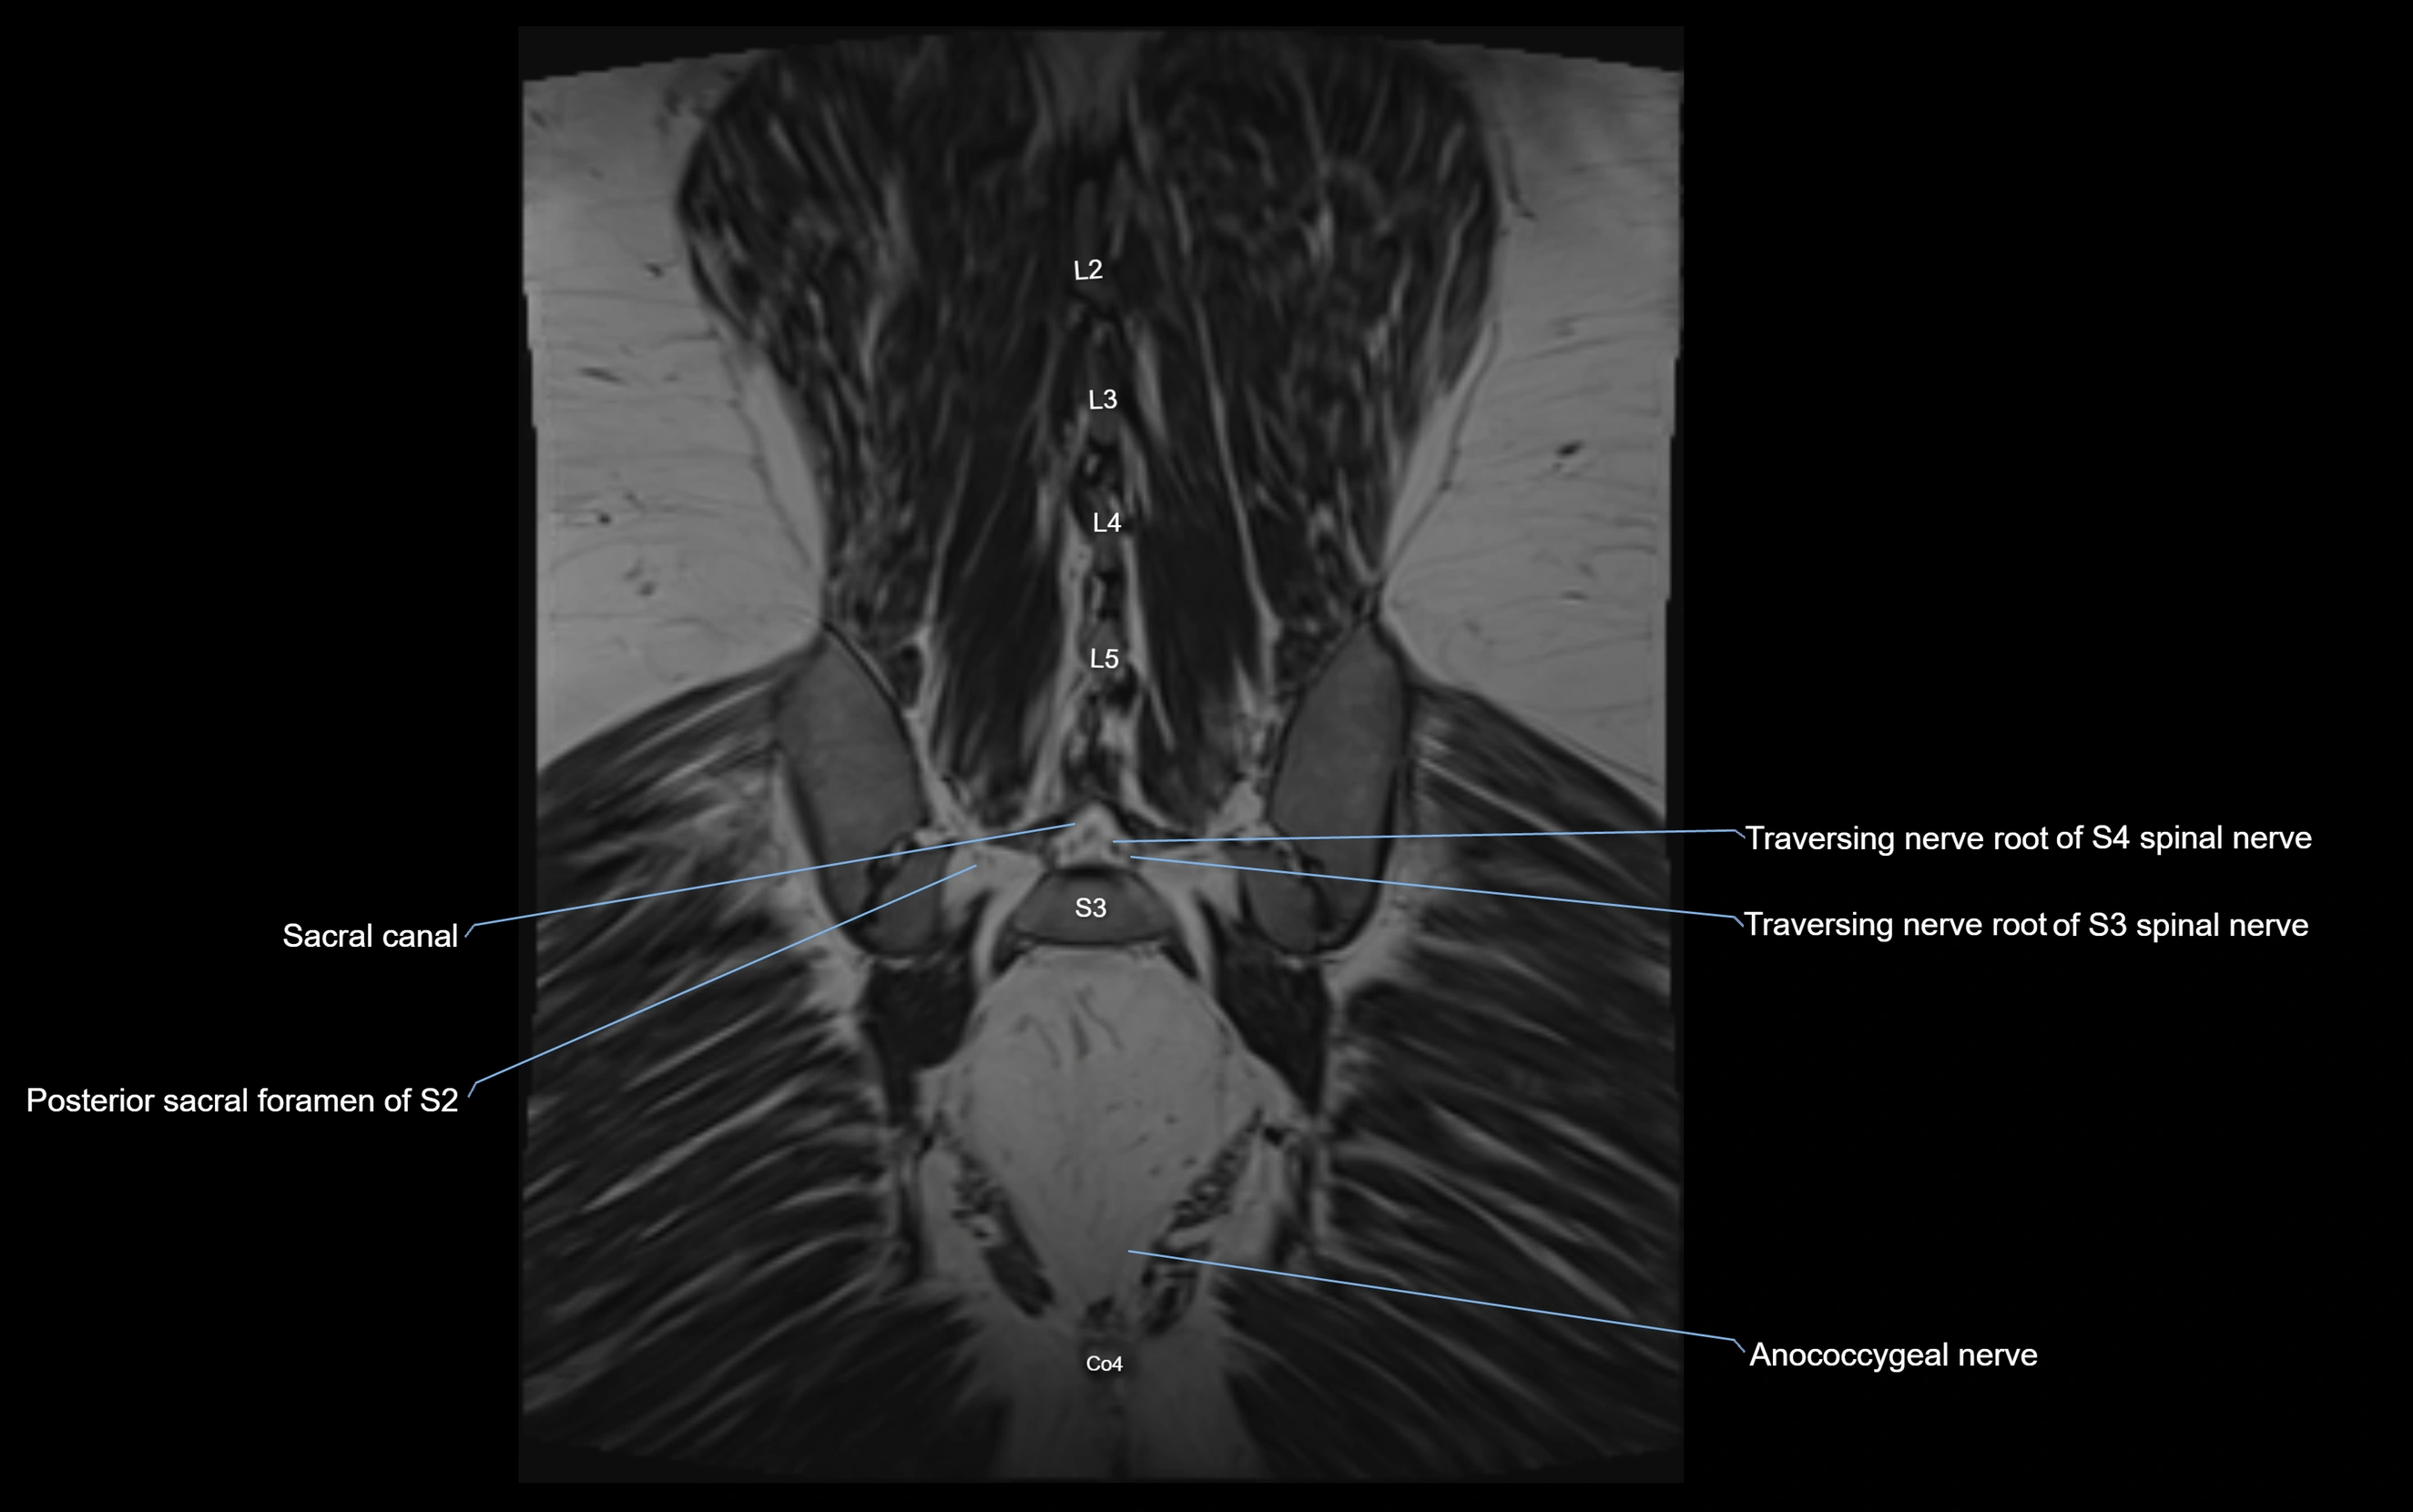

MRI image

image